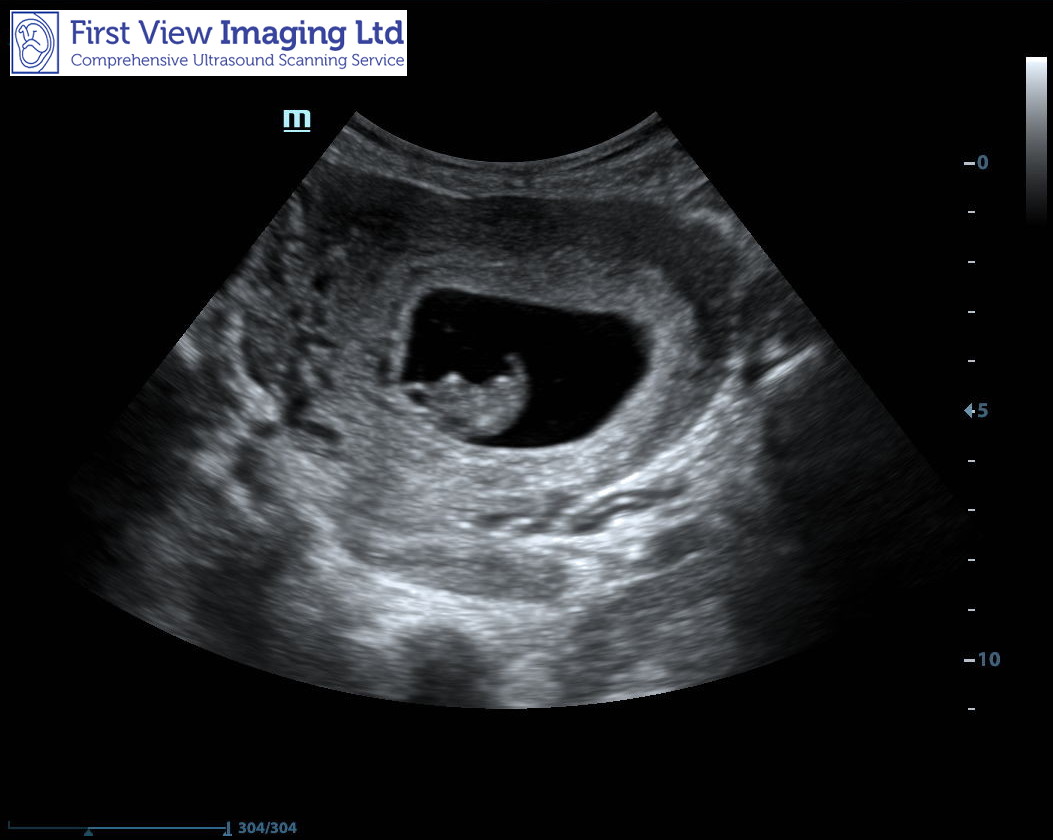

Abdominal. 8 weeks 6 days Attachment 41991